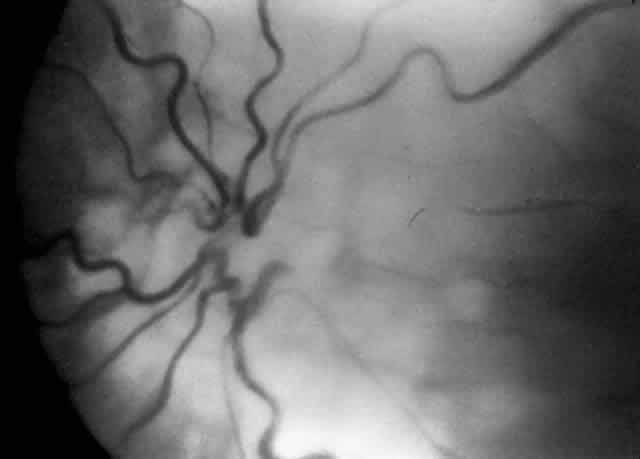

When first assessing a child's retinal detachment, one must judge the amount of effusive versus tractional detachment (Figs. 4 and 5). Scleral buckling would be considered for the child who shows a predominately effusive stage 4B detachment as opposed to a stage 4 predominately tractional detachment, for which lens-sparing vitrectomy may be recommended.24 For a child who has a great deal of retrolenticular touch, lensectomy/ vitrectomy and membrane peeling would be recommended. It appears that the “window” for lens-sparing vitrectomy may be rather brief. In one series, the postconceptual age of the lens-sparing vitrectomized eyes was 42.6 weeks, as opposed to 46.9 weeks for eyes that needed lensectomy/vitrectomy and membrane peeling. This small time difference in the postconceptual age shows the often rapid evolution of this detachment from one in which the lens is salvageable to one in which the lens is unsalvageable. This highlights the need for timely screening of eyes, identification of eyes with progressive disease, and rapid intervention.25

Fig. 4. A predominantly effusive stage 4B retinal detachment.

Fig. 5. A predominantly tractional stage 4B retinal detachment.